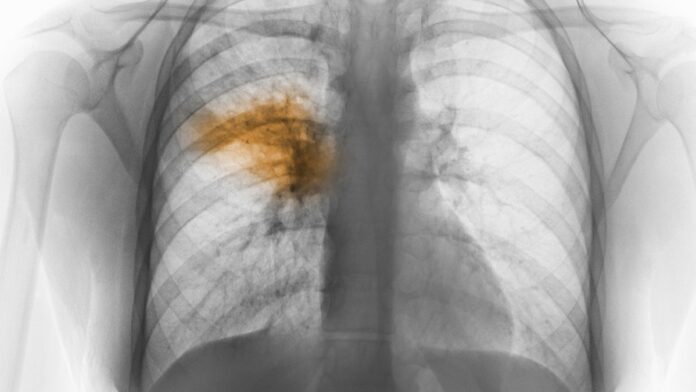

“Lo que tienen en común estos pacientes es el cuadro respiratorio severo con neumonía bilateral y compromiso en imágenes muy parecidas al COVID-19, pero eso está descartado”

Dr. Luis Medina Ruiz